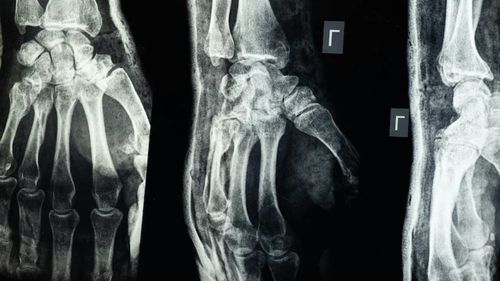

চীনের গবেষকরা দাবি করেছেন, তারা এমন এক ধরনের চিকিৎসা আঠা তৈরি করেছেন যা মাত্র তিন মিনিটেই ভাঙা হাড় জোড়া লাগাতে সক্ষম। নতুন এই ‘বোন গ্লু’ হাড় জোড়ার পাশাপাশি ভাঙা টুকরোগুলোও স্থির রাখতে পারবে এবং হাড় সেরে ওঠার পর এটি শরীরের ভেতর থেকেই স্বাভাবিকভাবে শোষিত হয়ে যাবে। ফলে ইমপ্লান্ট অপসারণের জন্য আরেকটি অস্ত্রোপচারের দরকার পড়বে না।

‘বোন–০২’ নামের এই আঠার উদ্ভাবন করেছেন পূর্ব চীনের ঝেজিয়াং প্রদেশের একদল গবেষক। দলটির নেতৃত্বে আছেন স্যার রান রান শ’ হাসপাতালের সহযোগী প্রধান অর্থোপেডিক সার্জন লিন শিয়ানফেং। তিনি জানান, সাগরের পানির নিচে সেতুর গায়ে ঝিনুক যেভাবে শক্তভাবে লেগে থাকে, সেখান থেকেই তিনি হাড়ের আঠা তৈরির অনুপ্রেরণা পেয়েছেন।